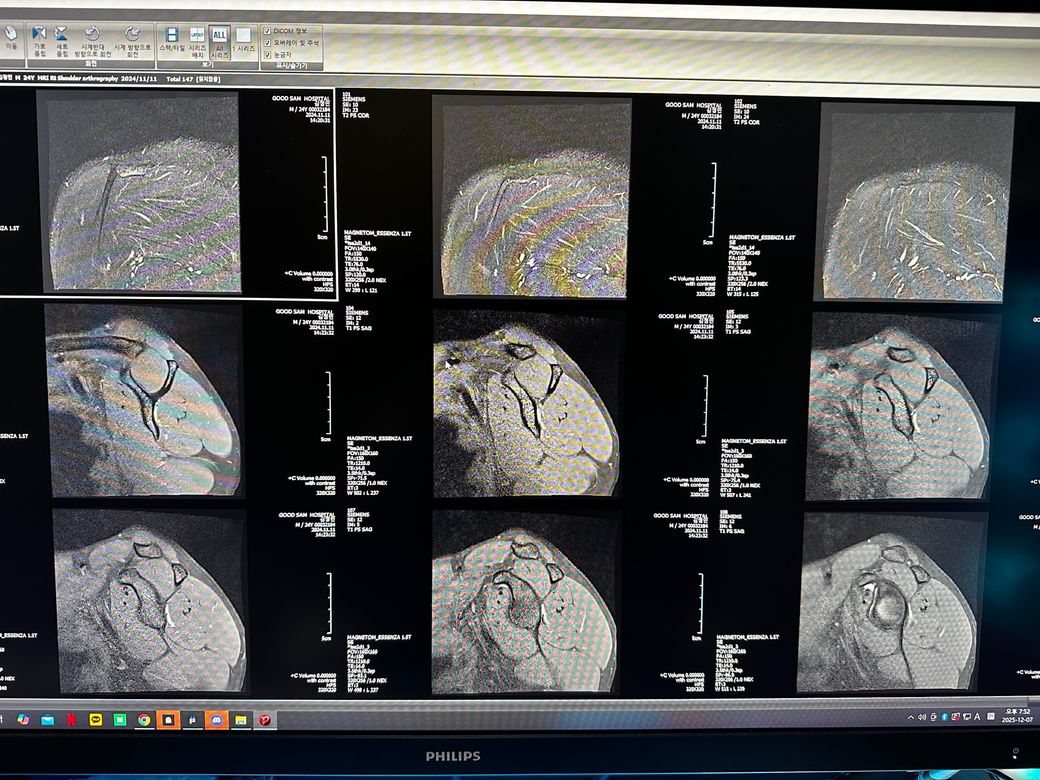

오른쪽어깨 관절mri좀 봐주세요 사진첨부입니다

오룬쪽어깨관절 엠알아이 결과좀 봐주세요

오른쪽어깨관절부분입니다

관절입니다

• 10번 째 사진

• 11번 째 사진

• 12번 째 사진

• 13번 째 사진

조영제가 들어간 것으로 보이며, "회전근개(특히 극상근) 파열이나 큰 손상은 뚜렷하게 보이지 않는 편"입니다.

관절와순(Labrum) 주변에 조영제가 퍼져 보이지만, "명확한 파열 소견은 사진만으로 단정 어렵고 경미한 손상.염증 가능성"은 있습니다.

관절 안쪽에 "약한 염증/활액 증가"는 있어 보이며, 충돌증후군 초기 형태 가능성이 있습니다.

힘줄 부위의 손상을 의심해볼 수 있는 구간이 있는 것으로 보이지만, 정확한 소견은 전문의 소견을 참고하심이 좋습니다.